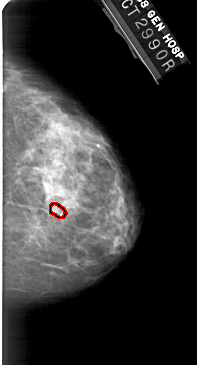

A_1949_1.RIGHT_CC

RIGHT_CC LINES 5101 PIXELS_PER_LINE 2746 BITS_PER_PIXEL 12 RESOLUTION 43.5 OVERLAY

FILE: A_1949_1.RIGHT_CC.OVERLAY

TOTAL_ABNORMALITIES 1

ABNORMALITY 1

LESION_TYPE CALCIFICATION TYPE PLEOMORPHIC DISTRIBUTION CLUSTERED

ASSESSMENT 4

SUBTLETY 3

PATHOLOGY BENIGN

TOTAL_OUTLINES 1

BOUNDARY